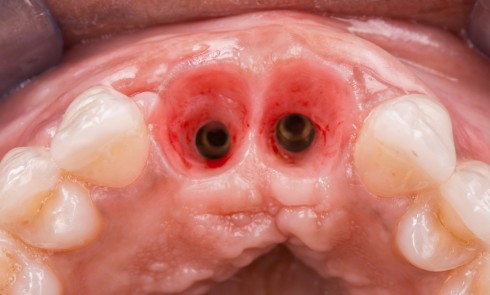

- Péri-implantite sur l’implant 47, diagnostiquée en août 2022

- Poches de 6 à 7 mm

La couronne a été déposée et une vis de couverture mise en place. La patiente a reçu un nettoyage supra-gingival général avec une attention particulière pour l’implant 47, et une irrigation locale avec du gel de chlorhexidine et du peroxyde d’hydrogène pour réduire l’inflammation des tissus. De l’amoxicilline (3 x 500 mg) a été prescrite, à commencer la veille de l’intervention chirurgicale.

La patiente est restée 4 semaines sans couronne. Après l’intervention chirurgicale, elle a entamé un programme de soins péri-implantaires et parodontaux, avec des visites de rappel tous les 4 mois.